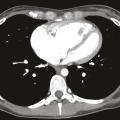

Sous le terme « hypertension pulmonaire » (HTP) est regroupé un ensemble de pathologies caractérisées par une élévation progressive des résistances vasculaires pulmonaires (RVP) pouvant aboutir à une insuffisance cardiaque droite.1,2 Son diagnostic est souvent tardif, du fait de symptômes non spécifiques. Cet article s’intéresse aux…

Chez les patients porteurs d’une insuffisance cardiaque (IC) gauche, la présence d’une hypertension pulmonaire (HTP), qui n’est pas une maladie mais une situation hémodynamique, est fréquente et est dite « post-capillaire » (HTPpc ou groupe 2 de la classification mondiale), au contraire des autres formes d’HTP.1

L’hypertension pulmonaire thromboembolique chronique (HTP-TEC) est une forme d’hypertension pulmonaire liée, d’une part, à une obstruction chronique des artères pulmonaires par du matériel fibreux, et, d’autre part, à une microvasculopathie secondaire. Elle survient le plus souvent après une ou plusieurs embolies pulmonaires (EP)…